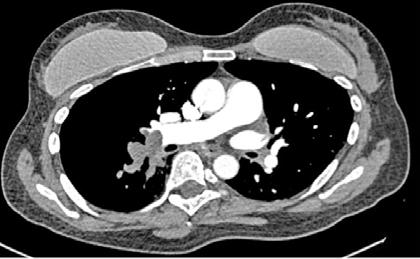

Mujer de 73 años con antecedentes de hipertensión arterial, trombopenia en contexto de lupus eritematoso sistémico, episodio de hipotiroidismo inducido por amiodarona y fibrilación auricular (FA) en estrategia de control de frecuencia cardiaca, anticoagulada con antivitamina K. Como fundamental antecedente cardiológicos destaca una valvulopatía reumática con afectación mitral, que inicialmente se reparó en 1997 mediante abordaje transapical (dejando como secuela aneurisma apical) y se recambió en 2007 por prótesis mecánica. Posteriormente, fue diagnosticada de doble lesión aórtica reumática con estenosis severa e insuficiencia ligera, con fracción de eyección preservada, pero insuficiencia tricuspídea severa e hipertensión pulmonar de predominio poscapilar. Ingresó programada para implante percutáneo de válvula aórtica (TAVI) vía transfemoral, con los principales condicionantes de bloqueo de rama derecha y altura límite de tronco coronario izquierdo (TCI), por lo que se administró clopidogrel 600 mg previamente al procedimiento.

Previo implante de marcapasos temporal yugular derecho se llevó a cabo el procedimiento. Durante la liberación de prótesis mediante inflado del balón, tuvo lugar la embolización supra-anular de la misma, dejando por un lado una insuficiencia aórtica severa y por otro lado ocluyendo parcialmente ambos troncos coronarios. Empleando doble acceso radial se enganchó la prótesis mediante un lazo y se desplazó hacia aorta ascendente, dejando hueco para la colocación de una segunda prótesis en situación correcta y evitando la oclusión de los ostium coronarios y troncos supra-aórticos. En ausencia de bloqueo auriculoventricular se retiró el marcapasos temporal, se evidenció un hematoma yugular derecho y, a través de analítica, se detectó anemización de 2,5 puntos. Mediante angiografía, se descartó enfermedad coronaria y, mediante ecocardiograma transesofágico, se confirmó normoposición de la prótesis, objetivándose al mismo tiempo una disección aórtica.

DIAGNÓSTICO Y ACTITUD INICIAL

Se realizó una tomografía computarizada (TC) con contraste de forma emergente, que mostró una disección aórtica iatrogénica tipo A focal de origen en la zona 0 del cayado con extensión al tronco braquiocefálico derecho (1) sin afectar al resto de troncos supra-aórticos, cayado o aorta descendente (Figuras 1 y 2); además del hematoma

yugular con signos de sangrado activo. La paciente fue trasladada a la unidad de cuidados críticos cardiológicos. Teniendo en cuenta el alto riesgo hemorrágico (necesidad de anticoagulación permanente, administración de clopidogrel previa al TAVR y sangrado activo cervical), el alto riesgo quirúrgico y la ausencia de compromiso neurológico y hemodinámico se optó por manejo conservador (2,3) con monitorización estrecha mediante técnicas de imagen cardiaca y control estricto de la presión arterial (4).

Figuras 1 y 2: Prótesis aórtica migrada y disección aórtica focal tipo A, de origen en la curvatura menor del arco aórtico (zona 0) hasta la bifurcación de la arteria braquiocefálica derecha; sin afectación de del resto de troncos supra-aórticos, del resto del cayado aórtico o de la aorta descendente.